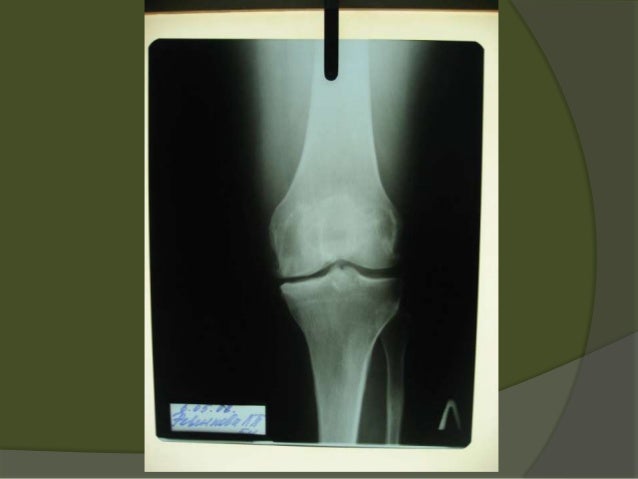

Knee osteoarthritis case presentation ppt

Knee osteoarthritis case presentation ppt image This image representes Knee osteoarthritis case presentation ppt.